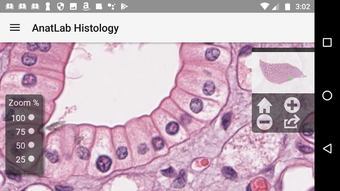

AnatLab Histology es una aplicación gratuita para Android desarrollada por Eolas Technologies Inc. que proporciona a los usuarios imágenes de diapositivas microscópicas de ultra alta resolución. Esta aplicación es una herramienta ideal para estudiantes, profesores, investigadores y el público en general. Con esta aplicación, pueden explorar el paisaje microscópico completo del cuerpo como si estuvieran mirando una colección de diapositivas reales en un microscopio físico. Tiene una función basada en la nube, la aplicación se puede acceder en cualquier dispositivo móvil Android, lo que la hace muy conveniente y accesible.

La aplicación ofrece una colección completa de imágenes de diapositivas microscópicas de histología que se pueden ver en ultra alta resolución. Las imágenes son de calidad excepcional y proporcionan una representación precisa del paisaje microscópico del cuerpo. La aplicación es fácil de usar y navegar, lo que permite a los usuarios explorar diferentes partes del cuerpo con facilidad.